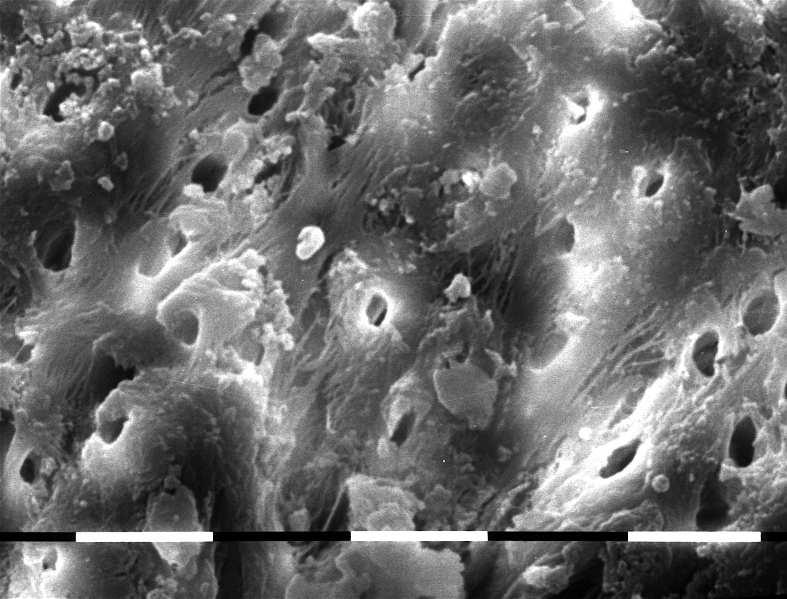

Fig.6 G1 representative sample image at medium third. 810nm diode laser irradiation at 2,5W pulsed mode, 10ms 50%on/off, in EDTA wet canal - 5sec three times: root canal surfaces are enough cleaned, with superficial vaporization of collagen fibers; opened dentinal tubules, some residual debris and smear layer still present.

Fig.7-8 G1 representative sample image at medium third. 810nm diode laser irradiation at 2,5W pulsed mode, 10ms 50%on/off, in EDTA wet canal - 5sec three times: root canal surfaces are quite cleaned and opened dentinal tubules, some residual debris and smear layer still present. Evidence of partially maintened organic matrix with exposed and intact collagen fibers both inter and peritubular.